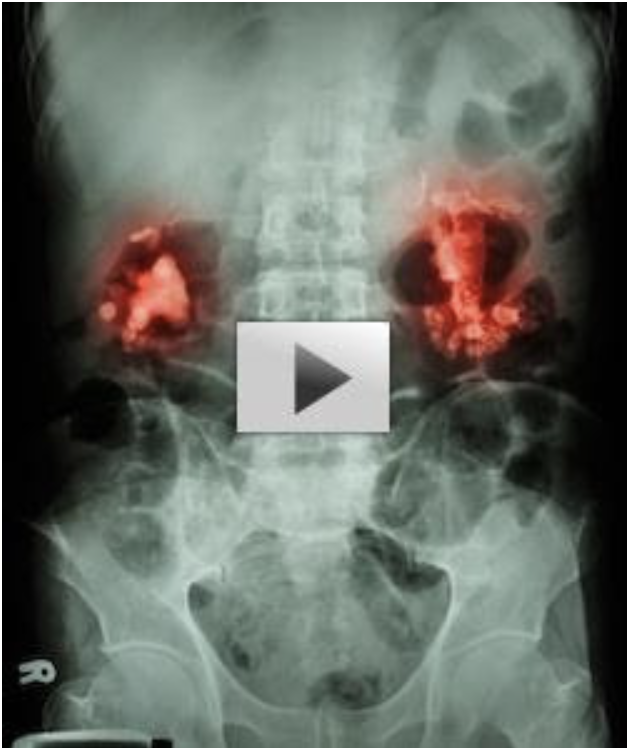

Kidney Scan Uncovers Real Cause Of Diabetes…

This changes everything we know about diabetes!

Scientists at the University of Iowa School of Medicine have uncovered what exactly triggers diabetes through this nuclear kidney scan…

This deeply disturbing thing is going on inside your kidneys at this very moment…

Wreaking havoc on your insulin levels.

Find out more here:

>> [CLICK HERE] The Real Cause Of Diabetes Hidden In Your Kidneys